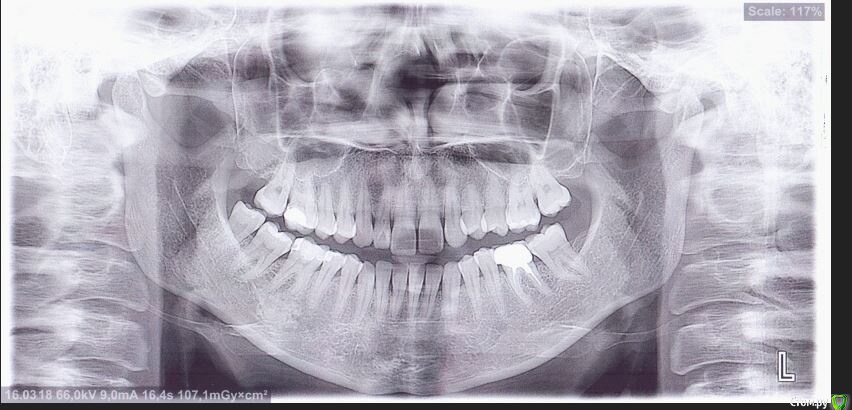

Мне 31 год. В детстве мне выбили верхний зуб 2-ку. Собираюсь лечиться брекетами, а потом вставлять имплант на место двойки. Но у меня есть еще проблеми с ВНЧС (с детства болит, хруст, щелчки), делала недавно КТ ВНЧС, диагноз артрит или артроз. Ходила к многим специалистам, все говорят разное. Надо ли проводить лечения капой моей дисфункции ВНЧС до установки брекетов или после установки брекетов?